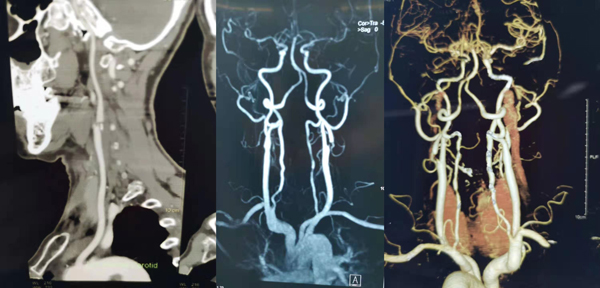

头颈部CT血管造影CTA显示:右侧颈内动脉起始部、两侧颈动脉环虹吸部钙化斑块形成,左侧颈动脉内动脉起始部混合斑块形成,右侧大脑前动脉近端局限性狭窄。

头颈部CT血管造影CTA显示:右侧颈总动脉分叉处及右侧颈动脉起始段混合斑块伴管腔重度狭窄、双侧颈动脉虹吸部硬化斑块伴管腔局部狭窄。

双侧颈动脉和椎动脉彩超显示:双侧颈动脉窦部硬化斑块形成。